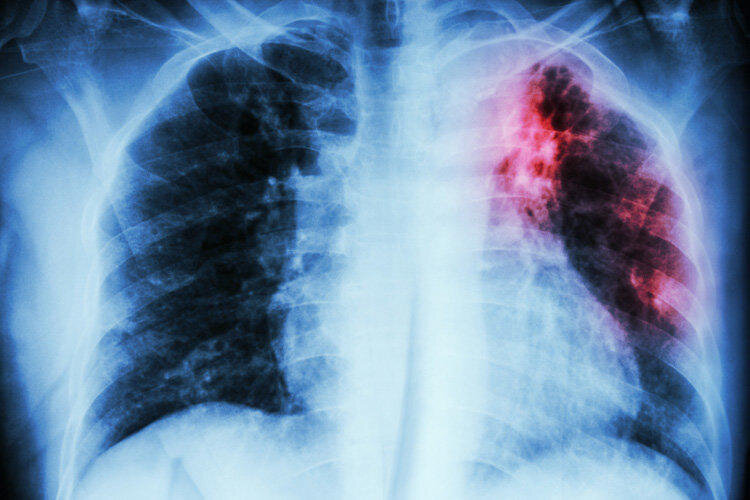

2. Туберкулёз поражает не только лёгкие, но и другие внутренние органы и даже кости!

8. Рентген лёгких и флюорография не гарантирует Вам абсолютную диагностику туберкулёза.